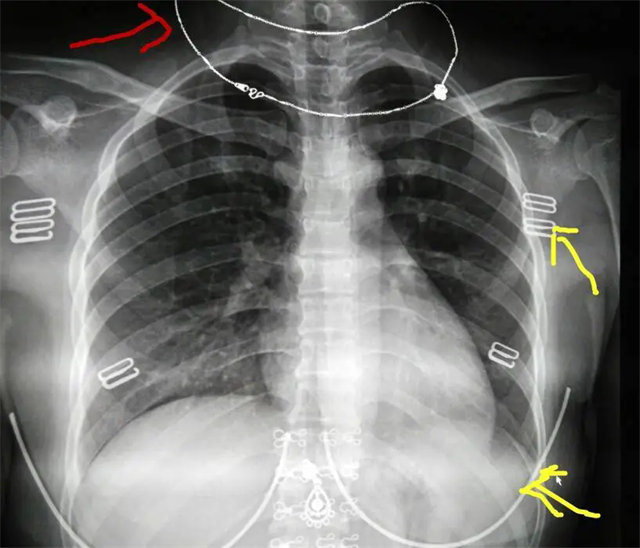

拍攝的不合格胸片的缺陷和解決方法

缺陷:左肩胛骨部分與左肺野重疊。

解決:使患者左肩旋前緊貼成像件重新曝光。